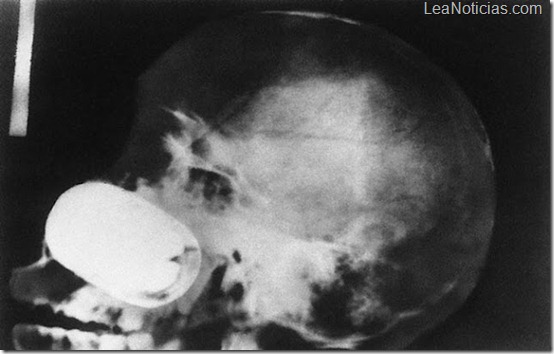

Un teléfono celular en el intestino de un prisionero.

Granada en el cráneo de un prisionero.

Una extraña radiografía donde se ve una botella de "Pepsi" en el ano de un hombre de 60 años.